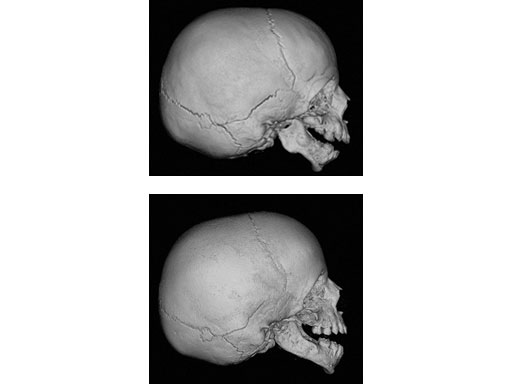

Multiplanar mandibular with curvilinear distractor in a 16-month old girl with Treacher Collins syndrome to improve mandibular and airway morphology and achieve tracheostomy removal.

Fig 3ab Pre- and postdistraction 3-D CT scans demonstrating curvilinear lengthening of the mandible.